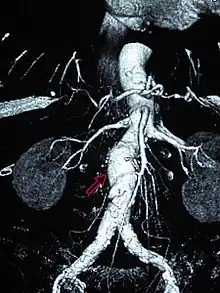

![]() | |

| CT reconstruction image of an abdominal aortic aneurysm (white arrows) | |